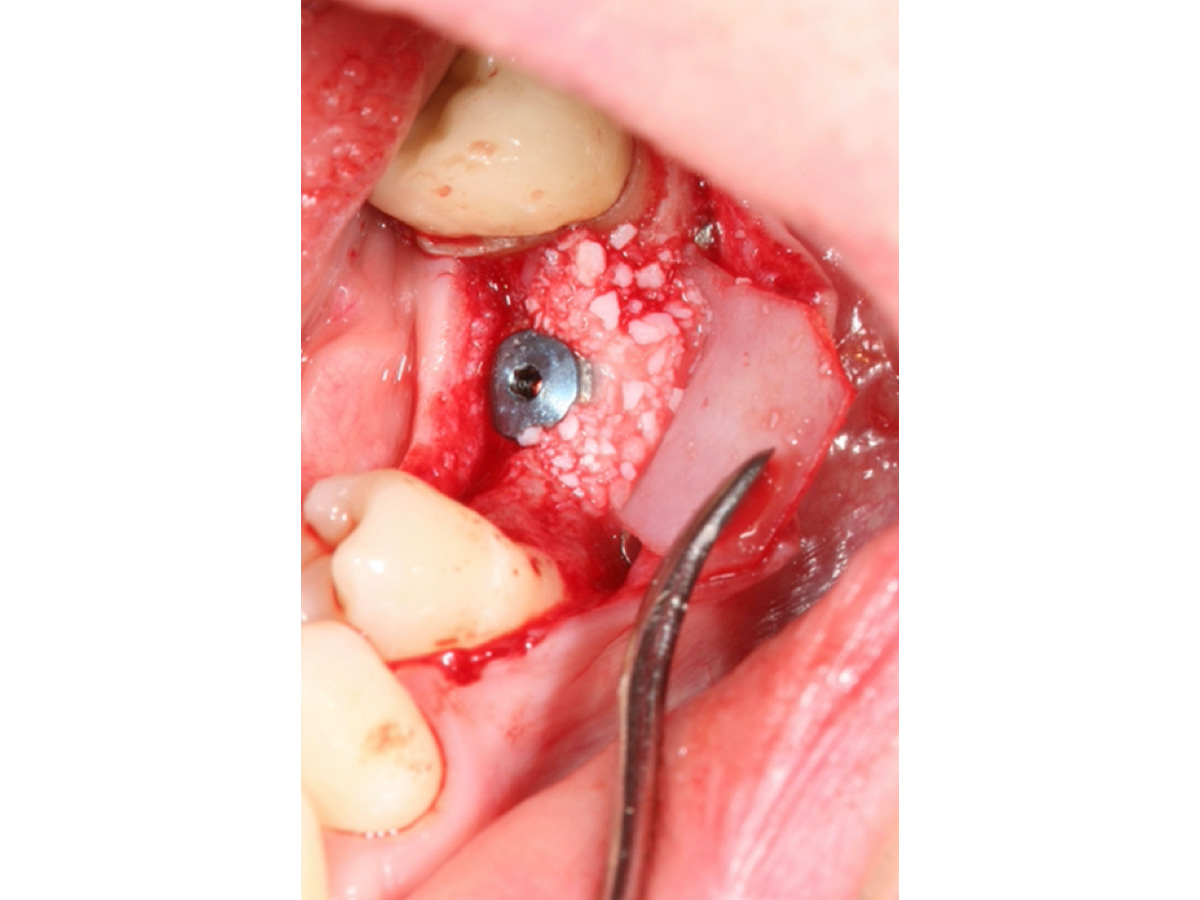

Nach Implantation wurde die zugeschnittene Bone Lamina positioniert und mit Pins fixiert, die Situation danach ist in Abb. 5 zu sehen. Mit dem Instrument wird demonstriert, dass eine „Tasche“ geschaffen wurde, die in Abb. 6 mit mp3® Knochengranulat aufgefüllt wird. Abb. 7 stellt dar, wie die Bone Lamina über den Kopf des Implantates auf den lingualen Anteil des Kieferkammes positioniert wird.

Abb. 8 zeigt die Situation vor dem Freilegen des Implantates und Abb. 9 die erfolgreiche Augmentation fünf Monate post operativ. Zu erkennen sind zwei Pins, deren Position sich im Niveau der Augmentation befinden und damit verdeutlichen, dass es zu keiner Resorption des ursprünglichen Augmentationsniveaus gekommen ist.

Nach Implantation: Positionierung und Fixierung der Bone Lamina.

Abbildung 5

Situation vor dem Freilegen des Implantates.

Abbildung 9

Augmentation nach fünf Monaten (klinisch).